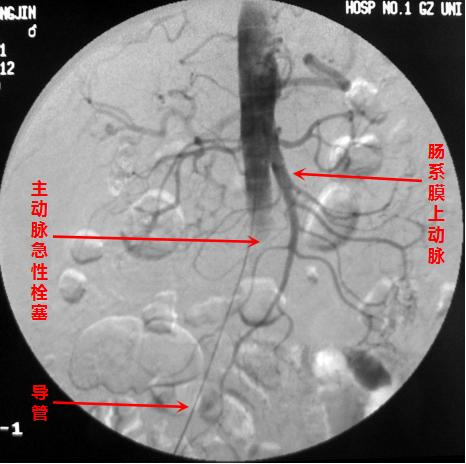

首先,通过介入血管插管,可以在远离病变、容易操作的部位简便实施。插入的细小导管可顺着血管走行,进行选择性血管造影,从而准确直观地显示出血管堵塞的部位、范围和程度,是诊断血管病变的“金标准”,为下一步的治疗提供有力的依据。

血管造影可清晰显示狭窄闭塞情况,腔内介入快捷有效